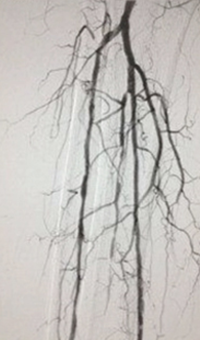

Thrombectomy of Occluded SFA - post-adjunctive treatment

Post-adjunctive treatment

Final angiogram showing flow post-treatment